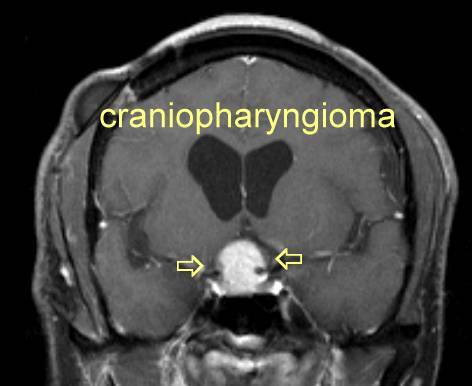

What can cause bitemporal hemiopia?

Craniopharyngioma (a tumour above the pituitary)

Pituitary adenoma

Suprasellar meningioma